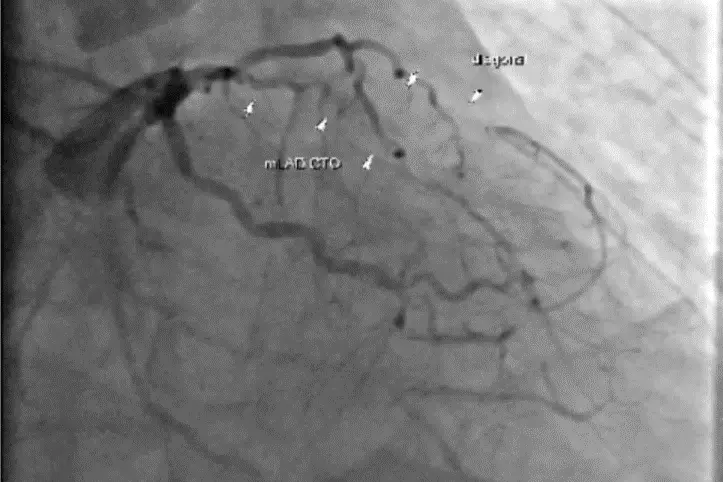

台北慈濟醫院心臟外科主治醫師楊凱文說,患者10多年前曾接受冠狀動脈支架手術,卻自行停用抗血小板藥物多年,導致血管逐漸阻塞,最終引發重度心臟衰竭,就醫後進行心導管檢查,發現3條冠狀動脈嚴重阻塞,左心室更出現5公分血栓,醫療團隊隨即展開冠狀動脈繞道手術及血栓清除術,並利用人工補片重建心室壁,術中同步放置暫時性左心室輔助器,以維持血流輸出。